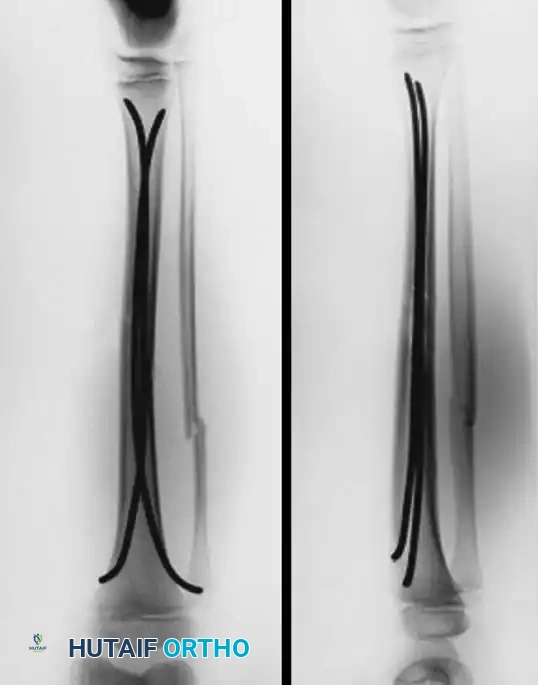

Pediatric fractures of the tibia and fibula generally possess an excellent capacity for remodeling and can predominantly be treated via closed reduction and cast immobilization. Operative intervention is strictly indicated when fractures are irreducible, open, associated with compartment syndrome, or involve the proximal or distal tibial physes with unacceptable displacement.

- Type I and II Fractures: Most can be managed with closed reduction and a bent-knee cast. However, posterior displacement requires meticulous reduction to relieve arterial tension. Unacceptable angulation must be corrected; malunion in older children will not remodel sufficiently.

Advanced imaging (CT with sagittal and coronal reconstructions, or MRI) is critical to determine the exact fracture geometry and the degree of articular step-off. Plain radiographs often underestimate the severity of the displacement, providing a false sense of security.

Fluoroscopic confirmation of anatomic reduction prior to definitive fixation.

Apply a well-padded, long-leg bent-knee cast (flexed to 30-40 degrees to relax the extensor mechanism). The cast remains in place for 4 to 6 weeks. At 2 weeks, a window is made for suture removal and wound inspection. Gentle, progressive mobilization of the knee is initiated between 4 and 6 weeks, tailored to the child's age and radiographic evidence of healing.